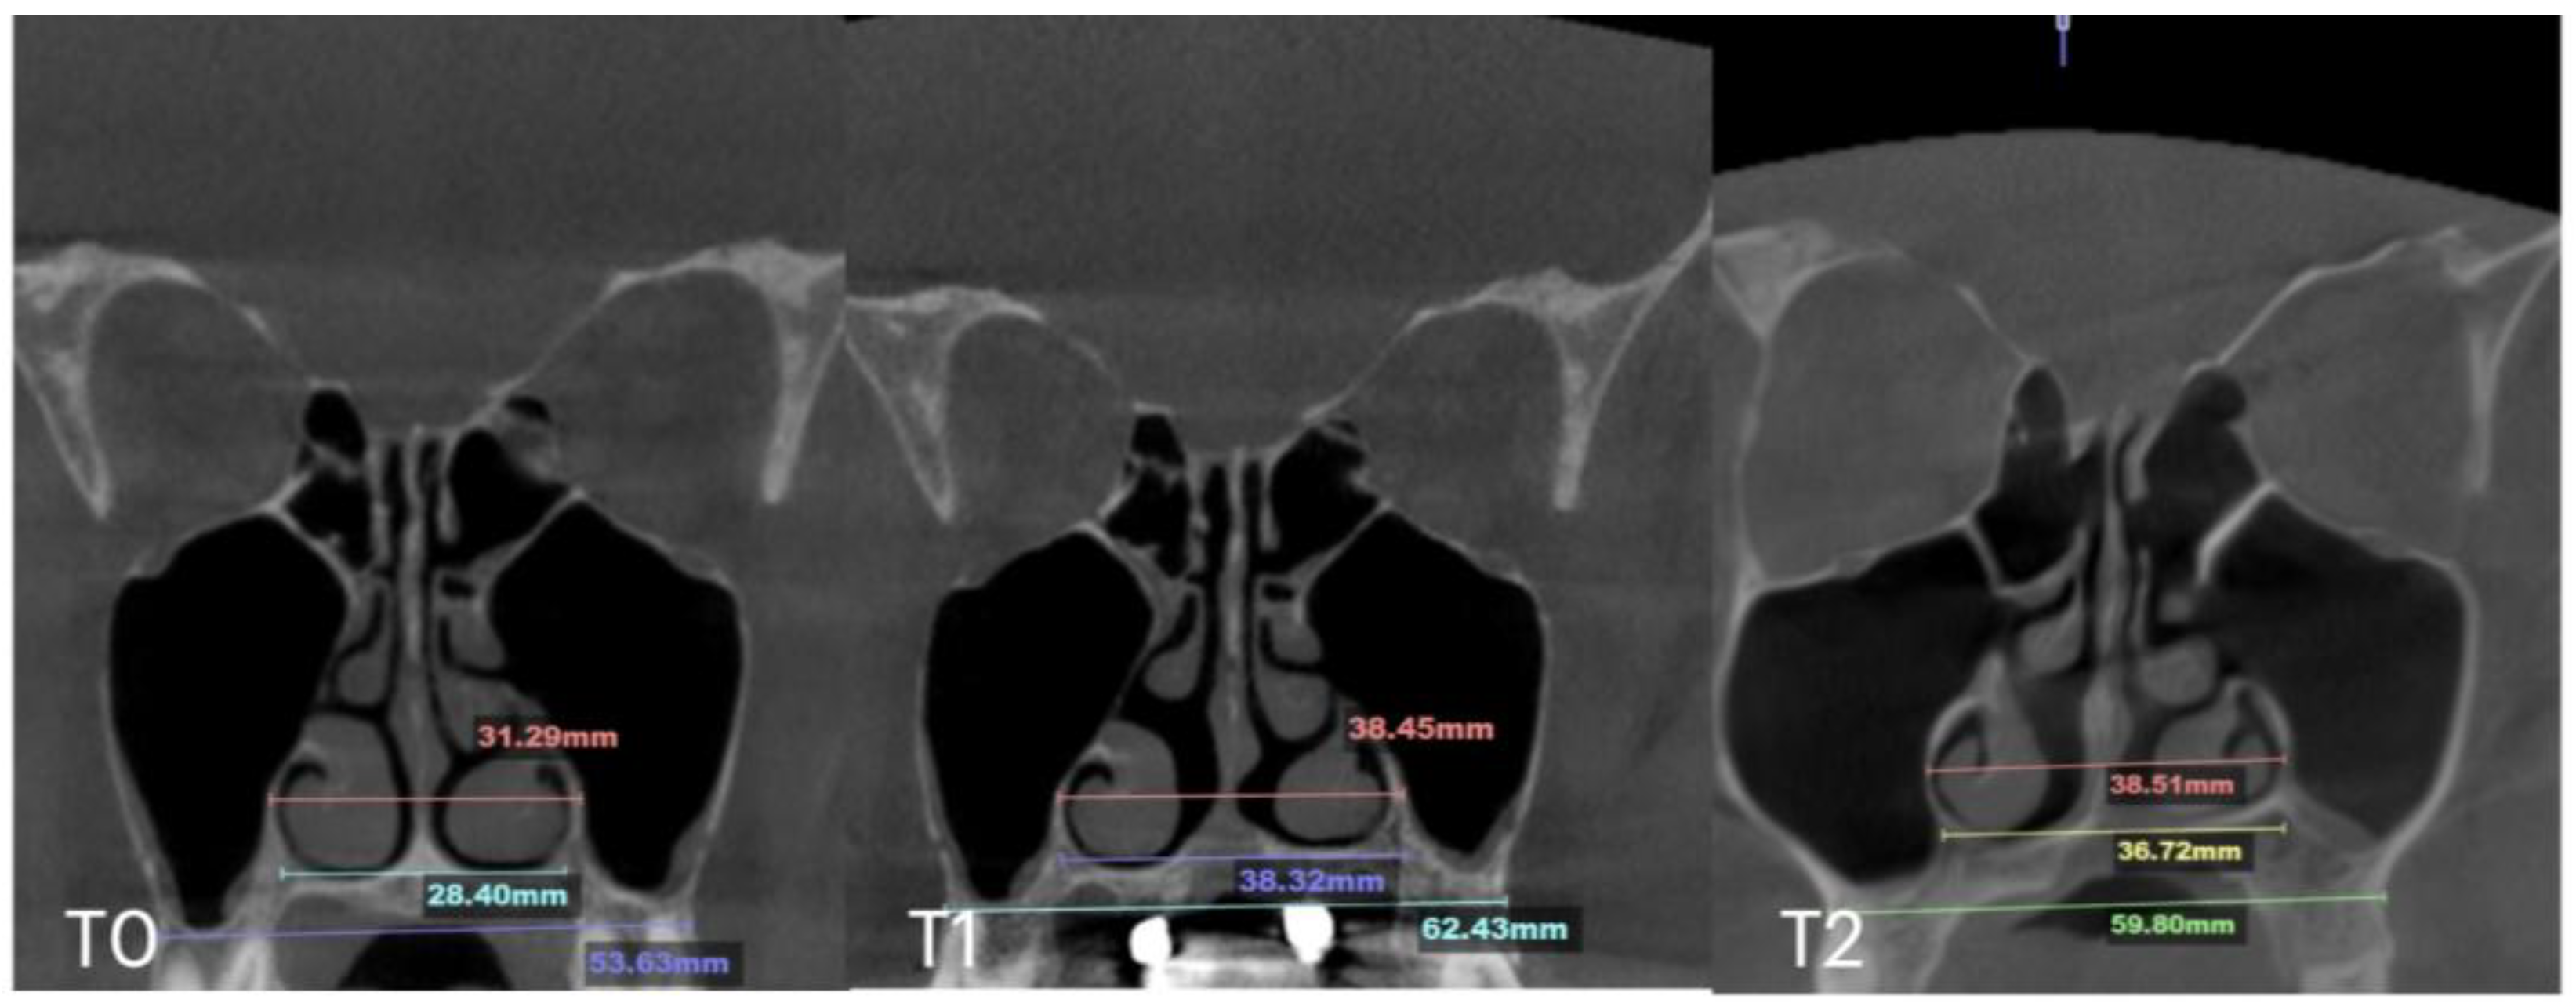

2.6. Case C: Bilateral Posterior Crossbite with Guide-Assisted Expansion

| Case C | 28.40 | 38.32 | 36.72 | 53.63 | 62.43 | 59.80 | 31.29 | 38.45 | 38.51 | 29.15 | 35.8 | 35.36 | 8.47 |